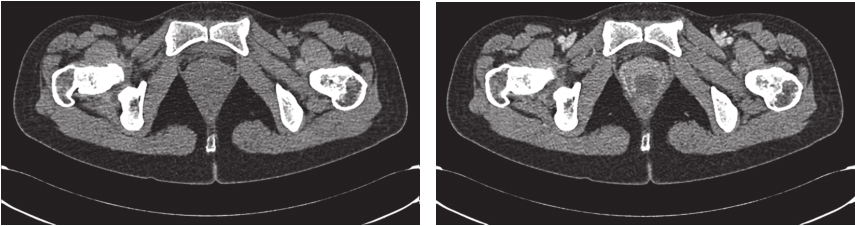

完善经直肠超声:直肠下段及肛管前壁距肛门1cm处可见不均匀低回声,大小约为4.3cm×3.7cm,内部回声不均,内部血流丰富、紊乱,可引出动脉频谱;肿瘤位于腹膜反折以下;耻骨直肠肌、肛门外括约肌完整。经腹超声见盆腔不均匀低回声,大小约5.9cm×4.8cm,与阴道分界不清。经会阴超声见盆腔不均匀低回声,大小约5.2cm×5.5cm,前方距皮肤约0.2cm,边界欠清,形态不规则,内血流信号丰富,可引出动脉频谱。完善PET-CT示:阴道下段与直肠前壁见类圆形肿物,大小约5.0cm×3.5cm×5.9cm,密度稍欠均匀,肿物与阴道、直肠前壁均分界不清,局部突向外阴。术前评估为潜在可切除性直肠GIST,考虑到肿物较大且与周围组织器官关系密切,直接切除有联合脏器切除的可能,且难以保全阴道和肛门功能,遂决定行术前靶向药物治疗。患者从2016年4月15日起,开始口服甲磺酸伊马替尼,400mg/d。此后规律复查,伊马替尼治疗1个月后复查增强CT(图2):直肠下段与阴道间可见类圆形混杂密度影,范围大致约4.2cm×2.5cm×2.6cm,病灶密度不均,其内可见液性密度区,增强扫描实性成分明显强化,病灶局部与直肠前壁及阴道后壁分界不清。对比首诊盆腔MRI,病灶较前缩小(Choi标准:PR状态)。伊马替尼治疗4个月后复查增强CT(图3):直肠下段与阴道间可见类圆形低密度病灶,大小约3.5cm×2.3cm×1.8cm,增强扫描可见轻度强化,病灶局部与直肠前壁及阴道后壁分界不清。对比前次复查:病灶较前略缩小(Choi标准:PR状态)。伊马替尼治疗6个月后复查增强CT(图4):直肠下段与阴道间可见类圆形低密度病灶,大小约3.9cm×2.1cm×1.9cm,增强扫描可见轻度强化,病灶局部与直肠前壁及阴道后壁分界不清。对比前片,病灶较前无明显改变(Choi标准:维持PR状态)。考虑患者术前靶向治疗已进行6月余,且药物治疗效果已达最大化,建议患者接受手术治疗。2016年11月1日门诊以“胃肠间质瘤,靶向治疗后”收入北京大学人民医院胃肠外科。

图2 伊马替尼术前治疗1个月后增强CT表现

引自:胃肠间质瘤典型病例诊治与解析.第1版.ISBN:978-7-117-30146-6.主编:陶凯雄 曹 晖

图3 伊马替尼术前治疗4个月后增强CT表现

图4 伊马替尼术前治疗6个月后增强CT表现